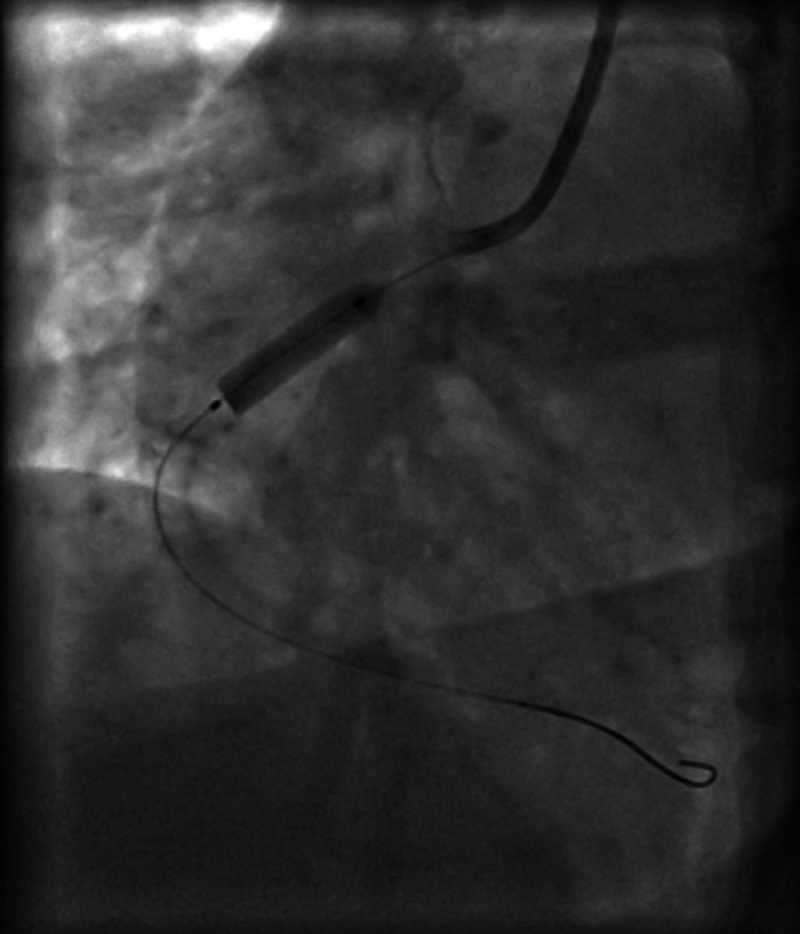

Figure 2.

Opening up of the right coronary artery on passing a wire.

Figure 3.

Balloon dilation of the right coronary artery and stenting.